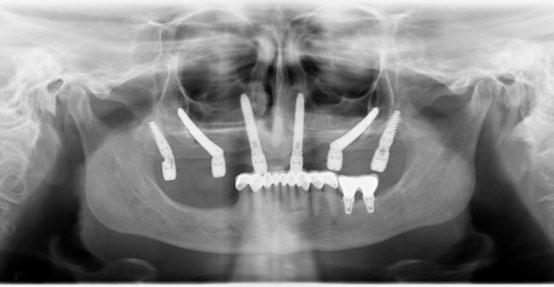

La planificación comienza con un CBCT para evaluar la densidad ósea del cuerpo cigomático, región pterigoidea y pared lateral de la cavidad nasal. Se realiza incisión crestal o vestibular extendida con colgajo mucoperióstico para exponer el reborde residual. Los implantes

cigomáticos se colocan con angulación hacia el cuerpo del cigoma desde el sector premolar, con perforación bicortical. Es esencial el estudio imagenológico con CBCT y escaneado intraoral para confeccionar una guía quirúrgica específica. En este caso se realizó una planificación virtual con software 3D para determinar la trayectoria ideal de los implantes transnasales y cigomáticos, asegurando que los ejes emergentes coincidan con el futuro diseño protésico.

Para los implantes transnasales se diseñó una guía quirúrgica impresa en resina que permite perforaciones precisas desde la cresta alveolar hacia la pared lateral nasal a una angulación de 30–45°, evitando penetración hacia la cavidad nasal sin dejar de despegar sus respectivas membranas y su correspondiente injerto. Esta guía se soporta en el reborde maxilar remanente con base en biomodelos impresos también en 3D.

lar, tuberosidad y cuerpo cigomático. Se despega la membrana nasal bilateralmente para evitar perforaciones de esta y se coloca creos™ xenogain de Nobel Biocare, un material de injerto óseo hecho de hueso bovino purificado. Con ayuda de la guía, se realizan las perforaciones transnasales hasta alcanzar la cortical nasal, obteniendo estabilidad tricortical. Posteriormente, se retira la guía y se colocan los implantes.

Para los implantes cigomáticos NobelZygoma, se realiza osteotomía bicortical con fresas de bola y calibradas hasta alcanzar el cuerpo del cigoma. El implante se introduce con torque elevado, asegurando anclaje en la cortical cigomática. Los implantes pterigoideos se colocan posteriormente con angulación de 70–75° hacia la placa pterigoidea, favoreciendo estabilidad tricortical.

La combinación de implantes cigomáticos con apoyos auxiliares transnasales y pterigoideos proporciona una rehabilitación más distribuida biomecánicamente. Los implantes cigomáticos aportan soporte principal en zonas posteriores, mientras que los transnasales actúan como pilares anteriores, reduciendo cantilevers protésicos. Los implantes pterigoideos permiten anclaje tricortical en región basal, mejorando estabilidad primaria en maxilas extremadamente neumatizadas. Por otro lado, la cobertura de los implantes cigomáticos con las bolsas adiposas de Bichat ofrece varias ventajas: aumenta el grosor de tejido blando periimplantario, reduce riesgo de mucositis por exposición y mejora la cicatrización en zonas sometidas a tensión. Diversos estudios han demostrado que esta técnica reduce la aparición de fístulas oroantrales y exposición de pilares cigomáticos. La literatura coincide en que la rehabilitación con múltiples vectores implantarios distribuidos disminuye las complicaciones mecánicas y biológicas, mejorando el pronóstico a largo plazo frente a configuraciones cigomáticas aisladas.

La colocación combinada de implantes cigomáticos con implantes transnasales y pterigoideos permite una rehabilitación fija completa incluso en maxilas altamente atróficas sin necesidad de injertos óseos. Al añadir hasta 4 implantes adicionales (2 transnasales anteriores y 2 pterigoideos posteriores), se crea una distribución hexagonal de pilares que brinda una estabilidad extraordinaria a la prótesis inmediata. Esta configuración re-

duce significativamente los cantilevers, distribuye mejor las fuerzas masticatorias y ofrece mayor resistencia rotacional, aportando una mayor sensación de seguridad tanto para el clínico como para el paciente. Otra ventaja clave es que esta técnica admite carga inmediata con altos niveles de éxito, favoreciendo la función estética y psicológica del paciente desde el primer día. El uso de las bolsas de Bichat para cubrir los cuellos de los implantes cigomáticos y transnasales, contribuye adicionalmente a la protección de tejidos blandos y a la disminución de complicaciones postoperatorias.